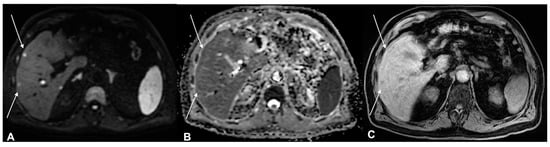

- Kawaguchi, M.; Kato, H.; Noda, Y.; Kobayashi, K.; Miyazaki, T.; Hyodo, F.; Matsuo, M. Imaging findings of malignant skin tumors: Radiological–pathological correlation. Insights Imaging 2022, 13, 52. [Google Scholar] [CrossRef] [PubMed]

- Kawaguchi, M.; Kato, H.; Tomita, H.; Hara, A.; Suzui, N.; Miyazaki, T.; Matsuyama, K.; Seishima, M.; Matsuo, M. Magnetic Resonance Imaging Findings Differentiating Cutaneous Basal Cell Carcinoma from Squamous Cell Carcinoma in the Head and Neck Region. Korean J. Radiol. 2020, 21, 325–331. [Google Scholar] [CrossRef] [PubMed]

- Kawaguchi, M.; Kato, H.; Tomita, H.; Hara, A.; Suzui, N.; Miyazaki, T.; Matsuyama, K.; Seishima, M.; Matsuo, M. MR imaging findings for differentiating cutaneous malignant melanoma from squamous cell carcinoma. Eur. J. Radiol. 2020, 132, 109212. [Google Scholar] [CrossRef] [PubMed]

- Sheng, M.; Tang, M.; Lin, W.; Guo, L.; He, W.; Chen, W.; Li, K.; Liu, J.; Xiao, C.; Li, Y. The value of preoperative high-resolution MRI with microscopy coil for facial nonmelanoma skin cancers. Ski. Res. Technol. 2021, 27, 62–69. [Google Scholar] [CrossRef]